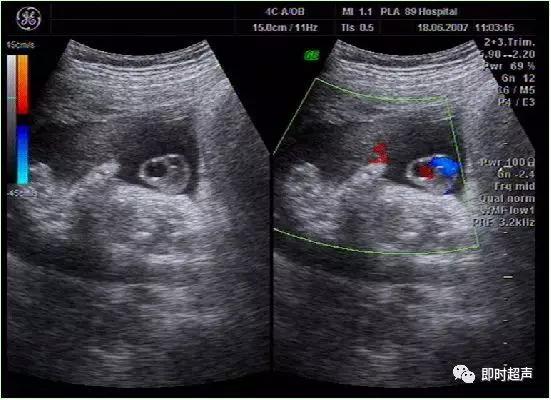

八、单脐动脉(SUA)

正常脐带内有两条脐动脉和一条脐静脉,供给胎儿营养。单脐动脉 , 指脐带内只有一条脐动脉和一条脐静脉,它是最常见的一种脐带异常。发生率约为0. 2% ~1.1%。

发生原因:可能为在脐动脉发育过程中,由于一条脐动脉发育不良或萎缩,或在早期暂时出现的单脐动脉期持续下去,都可能形成单脐动脉。

单脐动脉超声诊断

单脐动脉胎儿仅见一根脐动脉于膀胱一侧,经膀胱腹部横切面可判断左侧或右侧脐动脉缺如。羊水中脐带纵切面仅见两根血管并行或螺旋状排列, 横切时可见两个大小不一的圆环并行排列,彩色多普勒显示一红一蓝彩色血流信号。

单脐动脉胎儿结构畸形妊娠结局与染色体关系

单脐动脉导致胎儿发育异常的原因

单脐动脉扰乱了胚胎血流动力学,导致血汗管系统畸形以及影响了早期胚胎下半部的血液供应,引起泌尿系统、生殖系统、消化系统、中枢神经系统及下肢发育畸形。单脐动脉还造成胎儿循环障碍,使胎盘部分面积萎缩、绒毛水肿,回流血量减少,导致胎儿缺氧,继而引起胎儿发育不良、宫内发育迟缓。

超声诊断单脐动脉产前咨询和临床处理

✔ 单脐动脉者合并血汗管畸形发生率最高,应做心超查。

✔ 单脐动脉胎儿合并其他结构畸形的发生率明显高于正常胎儿,国外报道为 7% ~55%。

✔ 产前超声检出单脐动脉是比较常见的,右侧脐动脉缺失型多于左侧。

✔ 孕中晚期单脐动脉胎儿合并染色体异常发生率高达10% ,最常见的为 18 - 三体综合征。

✔ 对于单脐动脉伴有畸形胎儿建议常规做羊水穿刺或脐带血管穿刺进行染色体检查。

✔ 孤立性单脐动脉也就是无伴发畸形者,也应对生长发育进行认真评估,其宫内发育迟缓的可能性不容忽视,仍有建议行染色体检查的必要性,同时应密切监测其妊娠过程,并做好单脐动脉胎儿出产后的随访,防止产前不易发现的隐匿性畸形的存在。